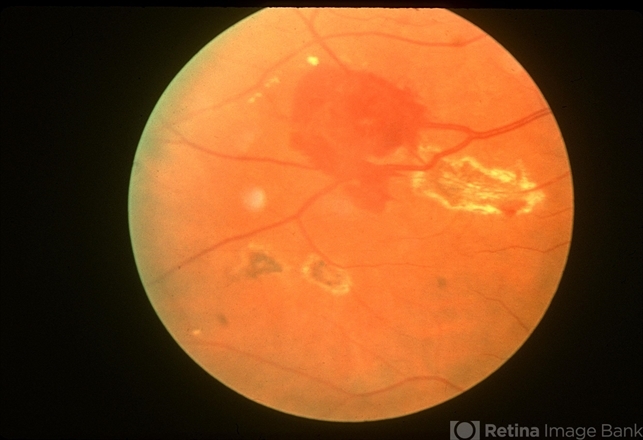

- retinal capillary hemangioma, feeder vessel

- Fundus photo of a retinal capillary hemangioma after treatment of the feeder vessel.